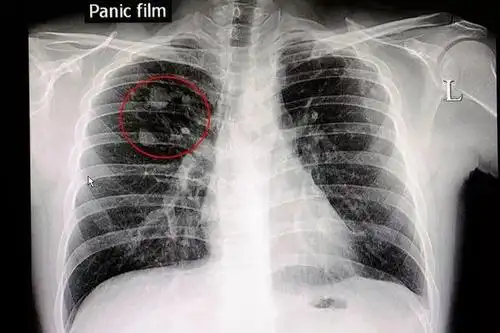

体检发现3毫米结节医生建议观察结果半年竟然成癌

如中国肺癌防治联盟肺结节诊治分中心管理; 5mm:这类结节叫微小结节